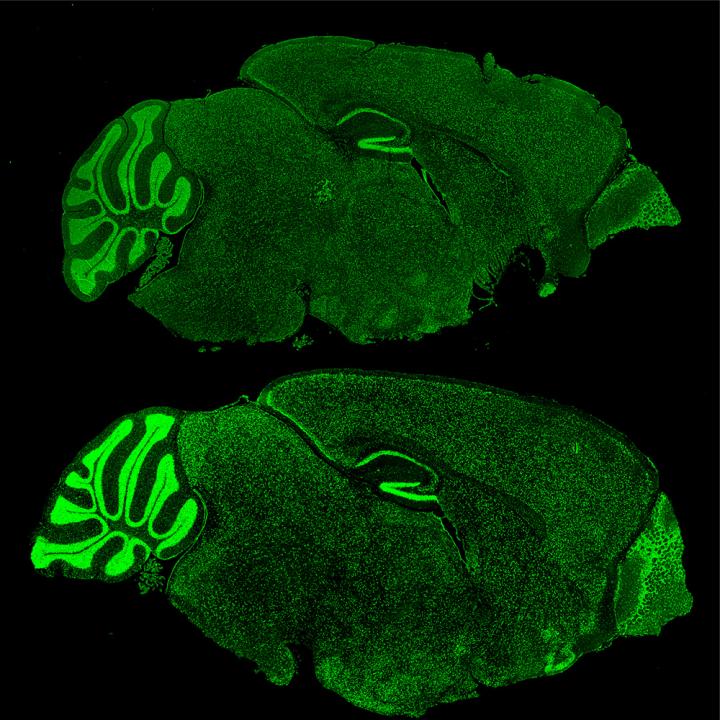

The researchers borrowed from the cancer biology field and used a drug to inhibit a specific chromatin remodeling protein known as Brd4. "The results were exciting. In cellular and animal models of Fragile X Syndrome, we saw a return to normal numbers of neuronal synapses and a decrease in behavioral symptoms," Korb says.